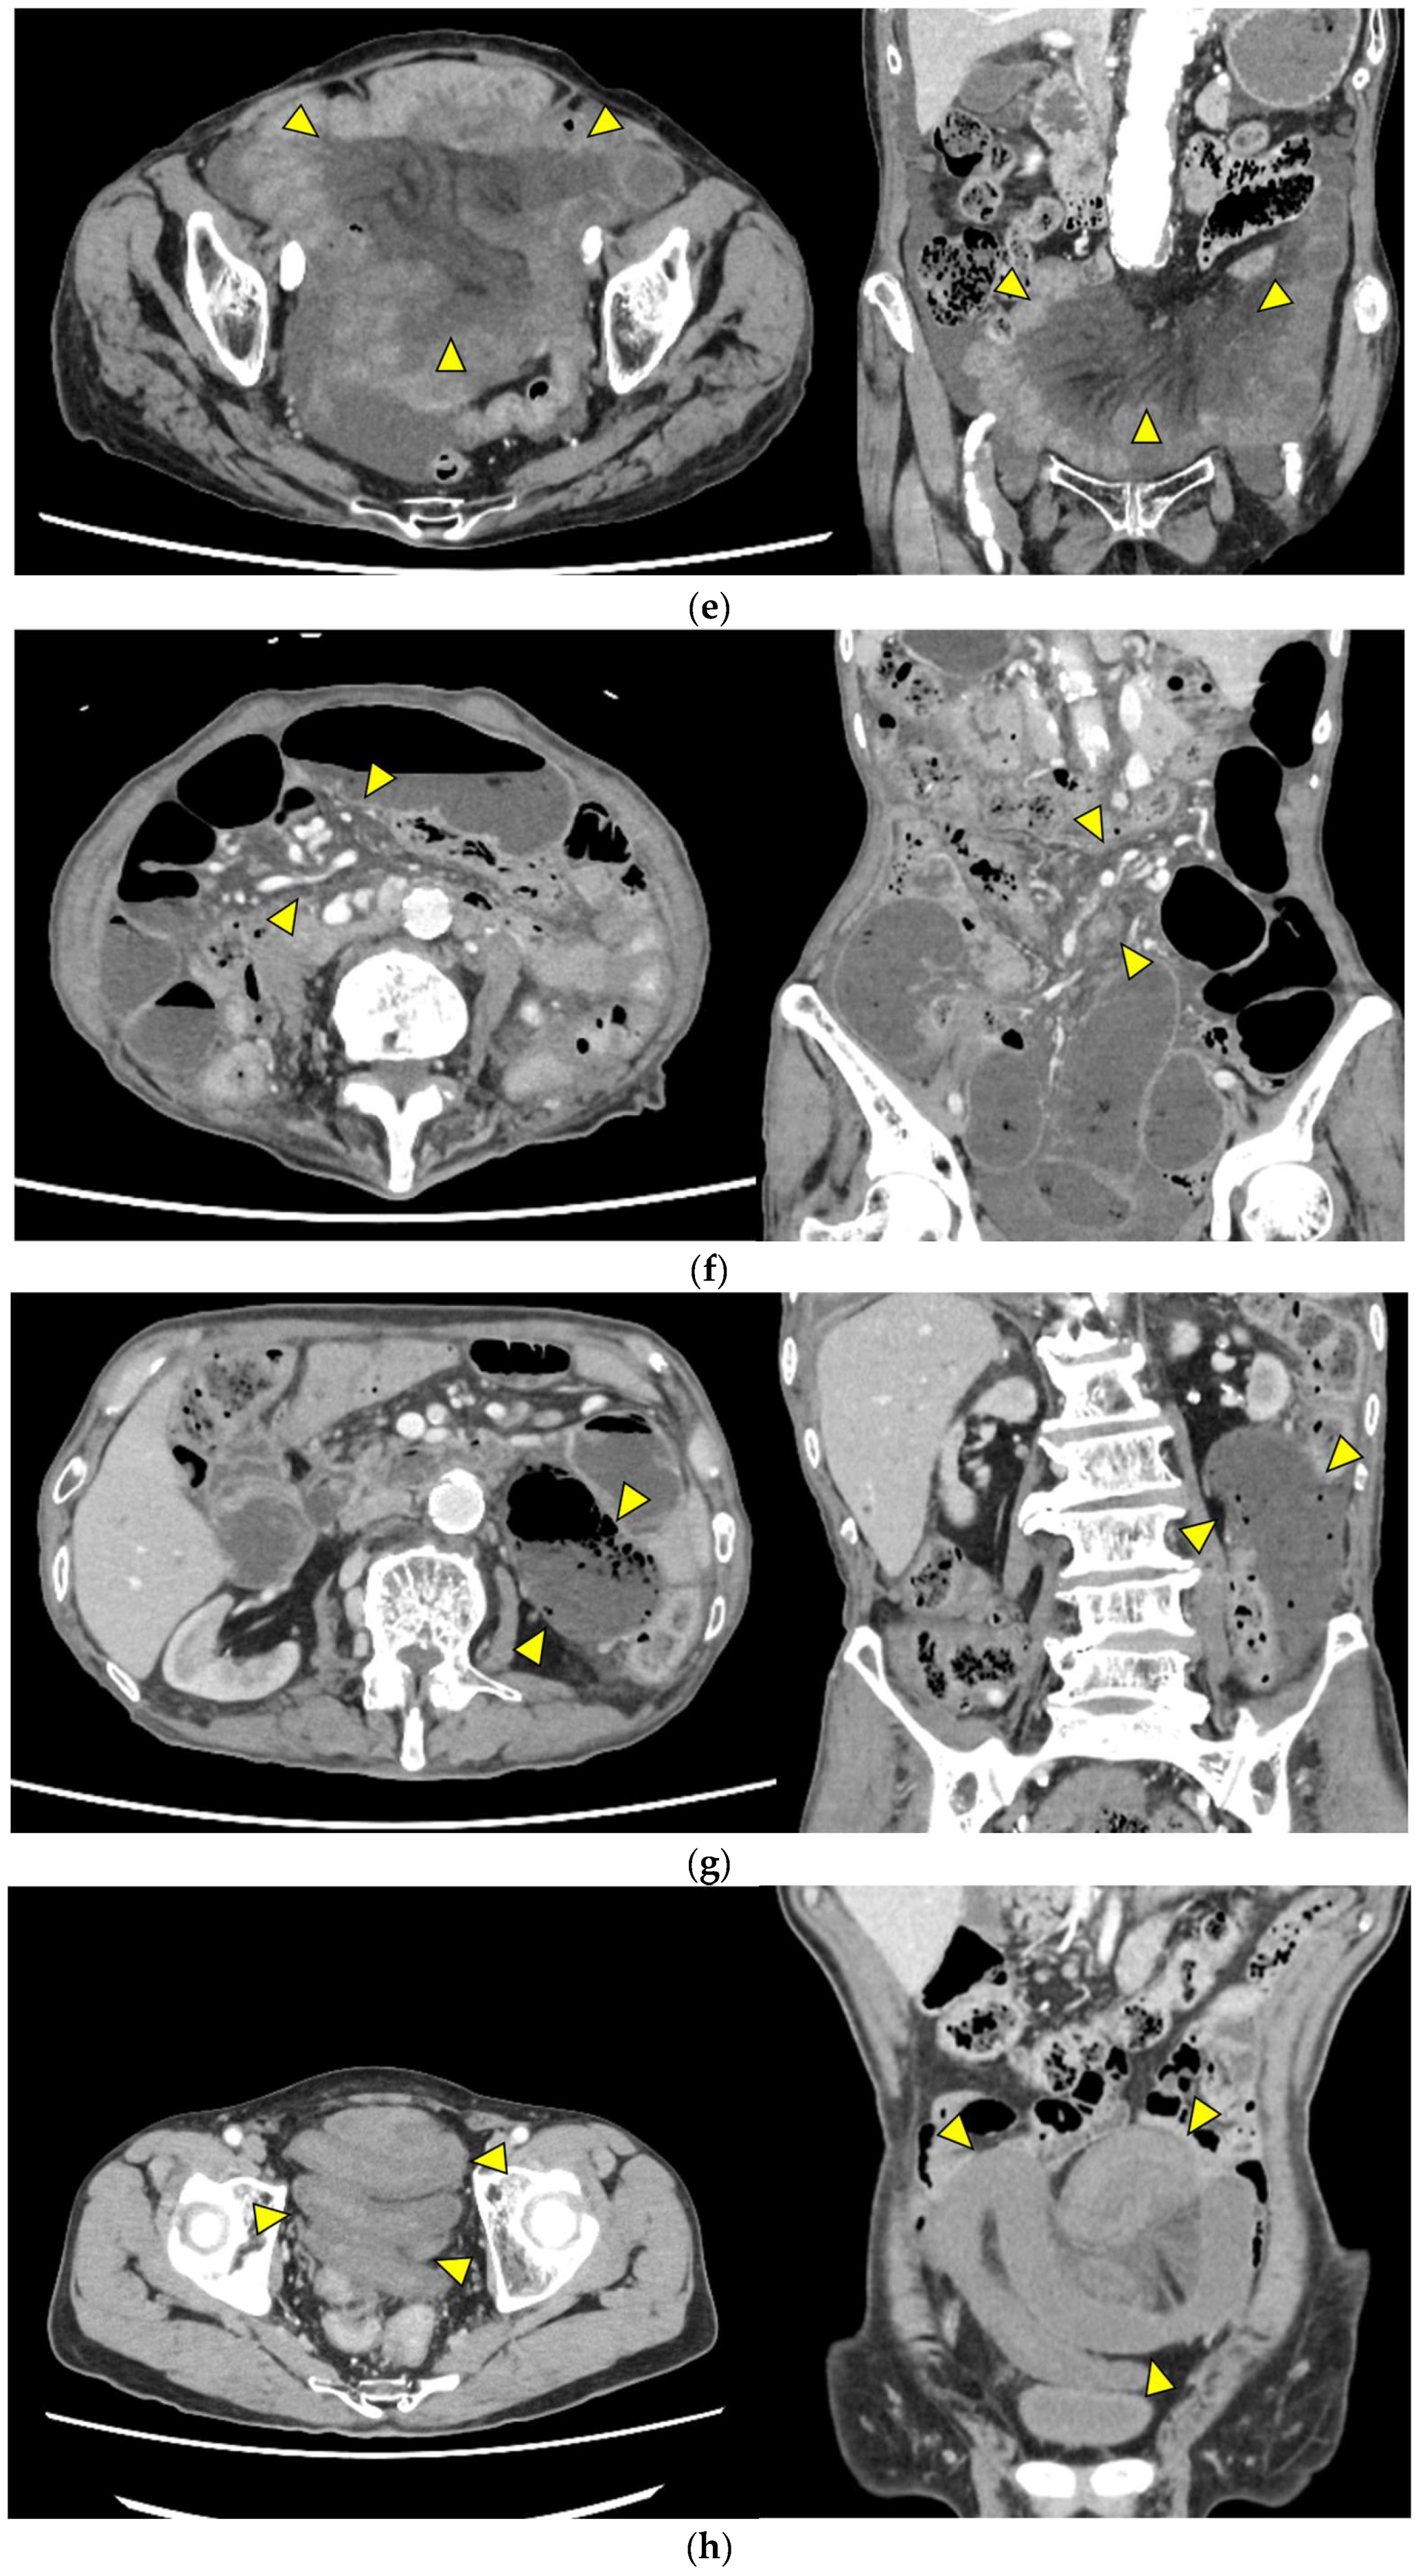

Representative images are presented in Figure 1.

• Closed loop (Figure 1a): A dilated U- or C-shaped bowel segment with two transition points in close proximity, often associated with radial distribution of mesenteric vessels. This configuration may carry a high risk of rapid progression to strangulation and ischemia, requiring prompt surgical consideration.

• Beak sign (Figure 1b): Gradual tapering of the bowel lumen or contrast column at the obstruction point, typically indicating torsion or sharp angulation. This sign localizes the obstruction and often reflects mechanical blockage due to adhesions or volvulus, which may progress to ischemia if left untreated.

• Whirl sign (Figure 1c): Swirling of mesenteric vessels and fat, suggestive of volvulus or twisted mesentery. Presence of this sign strongly suggests torsion with compromised mesenteric blood flow.

• Small bowel feces sign (Figure 1d): Mixture of gas and particulate matter (resembling feces) within a dilated small bowel loop proximal to the obstruction, indicating delayed transit. This sign indicates subacute or prolonged obstruction, but does not necessarily imply ischemia.

• Mesenteric edema (Figure 1e): Increased attenuation and stranding of mesenteric fat surrounding the affected loop, typically reflecting venous congestion. This is an early indicator of impaired venous outflow and increased risk of ischemia, requiring close monitoring and a low threshold for surgical intervention if clinical deterioration occurs.

• Mesenteric vessel engorgement (Figure 1f): Prominent or dilated mesenteric veins near the involved segment, suggestive of impaired venous outflow or strangulation. Venous congestion typically precedes arterial compromise, and the presence of this sign indicates evolving mesenteric ischemia.

• Absent bowel wall enhancement (Figure 1g): Complete absence of bowel wall enhancement on contrast-enhanced CT, which is highly suggestive of transmural infarction. This is a critical sign of irreversible ischemia and generally indicates the need for immediate surgical intervention.

• Blurred Kerckring folds (Figure 1h): Indistinct mucosal folds (valvulae conniventes) in dilated small bowel loops, often associated with ischemic edema. Blurring of mucosal folds reflects mucosal/submucosal injury from ischemia and impending bowel damage due to severe obstruction.

• Ascites (Figure 1i): Free peritoneal fluid, either localized around the affected loop or diffusely distributed, is frequently associated with advanced ischemia. Increasing ascites in the obstruction setting often indicates transmural ischemia or severe inflammation.

Figure 1. Representative CT findings suggestive of SSBO. Yellow arrowheads highlight the relevant findings. (a) Closed loop; (b) beak sign; (c) whirl sign; (d) small bowel feces sign; (e) mesenteric edema; (f) mesenteric vessel engorgement; (g) absent bowel wall enhancement; (h) blurred Kerckring folds; (i) ascites.